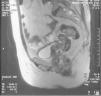

La resonancia magnética pone de manifiesto un útero atrófico sin masas. La vagina está totalmente deformada y muy aumentada de tamaño, debido a la existencia de una gran masa que infiltra todo el espesor de la pared de forma circunferencial, y que afecta incluso al fórnix y el tercio inferior. La masa contacta, impronta e infiltra la pared posterior de la vejiga, y también parece infiltrar la pared posterior de la uretra, sin atropamiento ureteral. No hay afección rectal. Se observan grandes adenopatías en la cadena ilíaca externa derecha y ambas cadenas inguinales. Se observan masas de diferente tamaño en el sigma, con las mismas características que la masa vaginal y que pueden corresponder a implantes peritoneales (fig. 4).

Fig. 4. Resonancia magnética pelviana, corte longitudinal, gran masa vaginal que infiltra ampliamente la pared vaginal posterior.